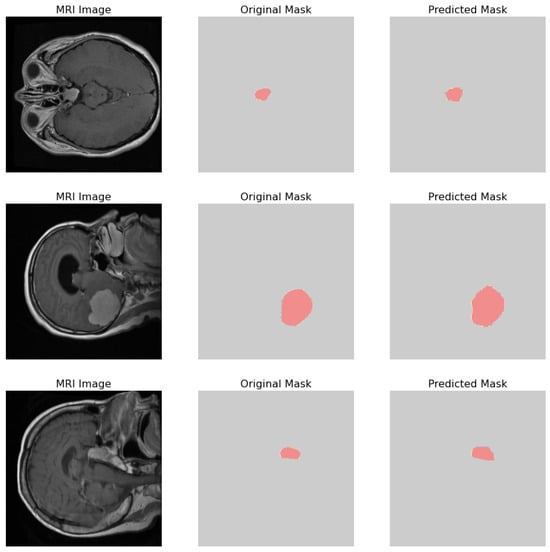

- Original Image: The pipeline receives the MRI scan as its initial input, showcasing a comprehensive cross-sectional view of the patient’s brain and potential pathological features.

- Ground Truth Mask: Next to the original image is the ‘Ground Truth Mask’, meticulously annotated by clinical experts to delineate the regions of clinical significance, such as lesions or tumors.

- Predicted Mask: The segmentation branch of our pipeline then predicts a mask, endeavoring to replicate the expert annotations by encapsulating the region of interest highlighted in the MRI scan.

- Predicted Class: Simultaneously, the classification branch assigns a ‘Predicted Class’ to the scan. The labels, denoted by integers (0, 1, 2), classify the scan into categories that reflect the model’s interpretation of the underlying pathology.